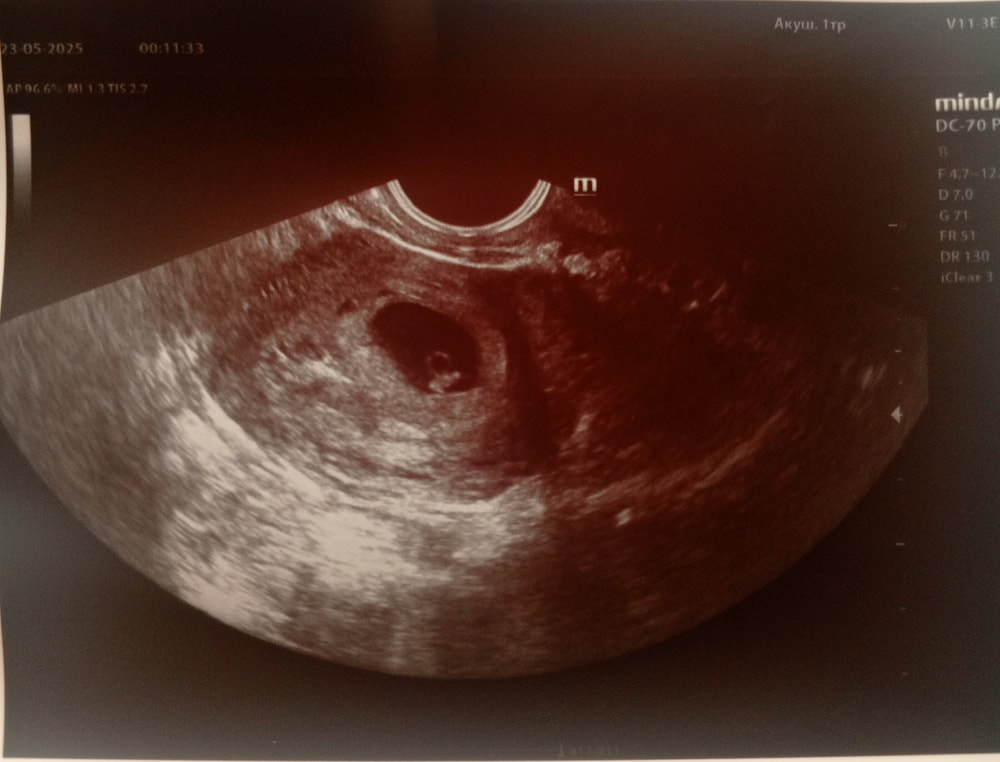

Первое узи

УЗИ, КТГ, доплерСходила сегодня на первый прием врача. Беременность 5-6 недель. На узи сказали, что видят и желтое тело, и белое тело и кружочек, что должен быть, но сказали рано для сердцебиения. Позвали через 2 недели посмотреть. Но врач сказал - цитирую : всё хорошо, так и должно быть. С сыном не помню когда впервые услышали сердце.

В 5 нед 6 дн делала - плодное яйцо с венчиком ("колечко с бриллиантом"), эмбрион не увидели, сб не было. В 7 нед 2 дн - и эмбрион уже нашли, и сб +

Юлия, спасибо большое за поддержку 🫶. У меня вот тоже сегодня показали только колечко было видно. Надеюсь на лучшее и отпугиваю дурные мысли 🙏🏻